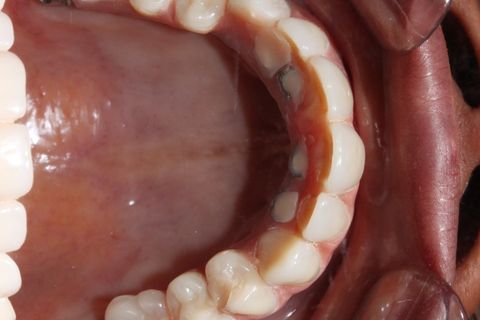

oclusal - extensão da barra polida para captura dos implantes pterigóides.

2 - Notar pequenos espaços, sempre convexos para introdução de fio dental específico( super floss) e/ou irrigador oral(water pik)